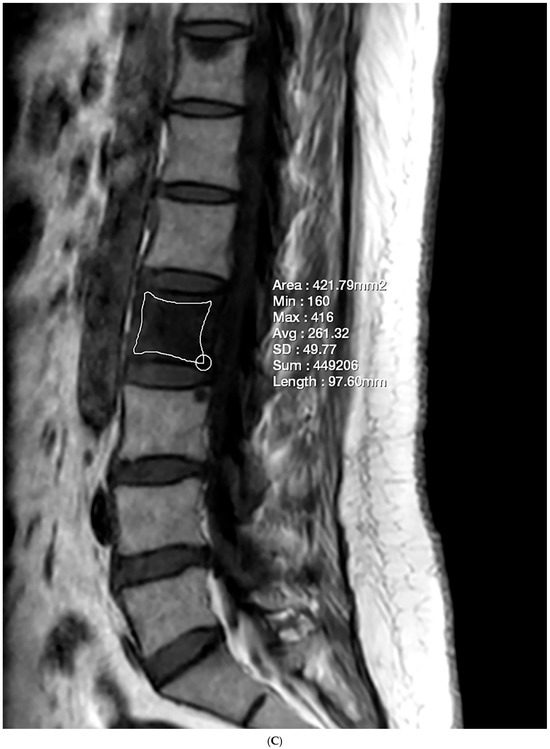

Figure 1.

Lumbar spine MRI of a 59-year-old male. (A) Fat fraction (FF) measurement on gradient-echo (GRE)-based chemical-shift-encoded magnetic resonance imaging (CSE-MRI). The FFGRE in this patient was 66.91%, representing the median value of the L1–L4 vertebral bodies. (B) FF measurement on spin-echo (SE)-based CSE-MRI. The FFSE was 85.84%. The numbers in the figure indicate the ROI numbering in the EXPRESS program. (C) Measurement of the vertebral bone quality (VBQ) score was calculated by dividing the median value of T1-weighted signal of L1–L4 vertebral bodies by the cerebrospinal fluid (CSF) signal at the L3 level. The VBQ score for this patient was 2.63. (D,E) FF color maps were created through GRE- and SE-based CSE-MRI.